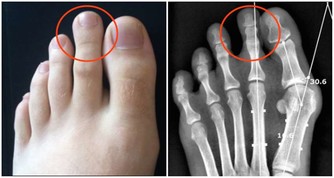

掉髮

睪固酮、甲狀腺激素水平異常時,易引發脫發、掉發現象,建議出現異常性大量掉發時,盡快咨詢專業醫生。